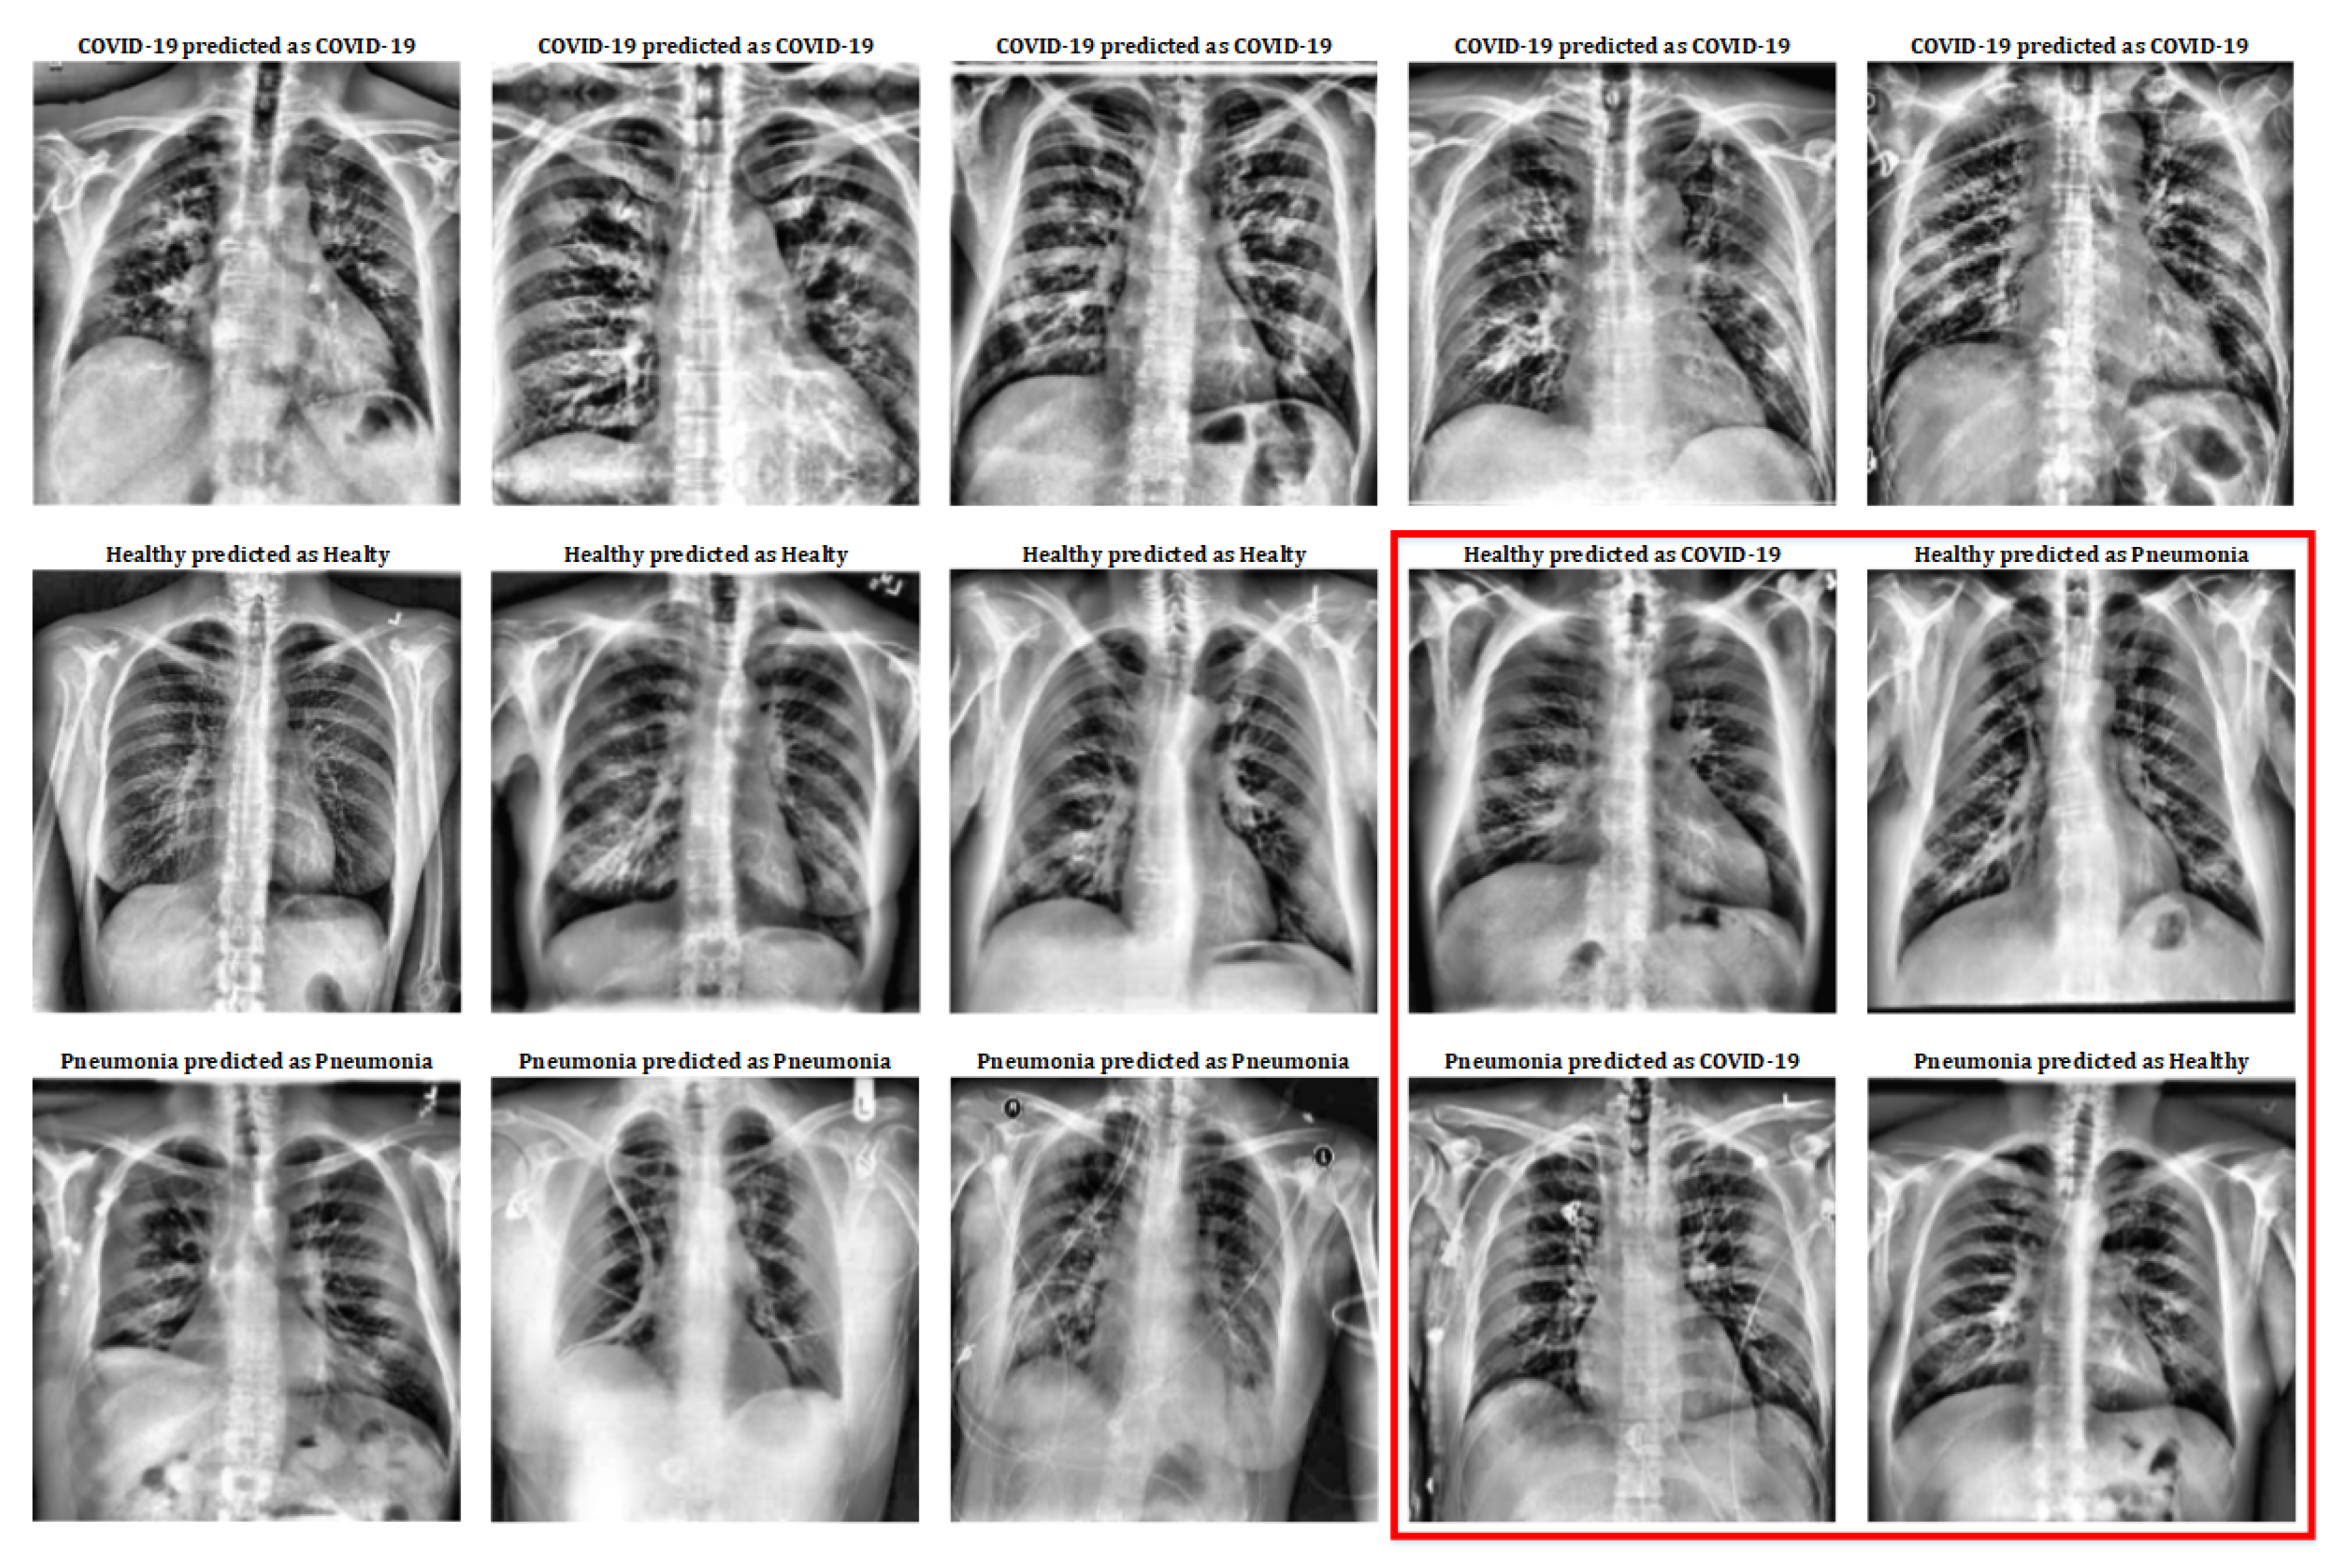

Although the numerical results obtained reflect the goodness of the implemented system, it is very interesting to observe the X-ray images that have been used on it to appreciate the similarities and differences between patients with COVID-19, patients with pneumonia and healthy patients. Some of the images used in this work and the classification results of the system can be seen in Figure 4.

Figure 4.

Classification results on X-ray images.

In Figure 4, the first row shows five COVID-19 pulmonary X-ray images; the second row shows five healthy pulmonary X-ray images; and the third row shows five pneumonia pulmonary X-ray images. As can be observed, the first row only contains images that have been classified correctly (remember that COVID-19 class has a 100% success in the classification results, so no mistake has been done in this class). Healthy and Pneumonia classes do not have a 100% success rate, that is why this figure includes some images that have been wrongly predicted. So, Figure 4, includes a subset of the dataset used for this work with all the different cases (positive and negative) in order to show the positive and negative aspects of this classification mechanism.

If we observe deeply Figure 4 in order to extract the medical details that cause these classes distinctions, a severe inflammation in the alveoli and bronchioles can be distinguished in images of COVID-19 patients; this is related to the damage that these patients suffer in their lungs. As for healthy patients, both the alveoli and bronchioles are less inflamed. Finally, those patients with pneumonia show appreciable inflammation too, but not as marked as in patients with COVID-19.

Even so, in the red box some erroneously classified cases can be seen. Among these cases, images of healthy patients are shown who, due to inflammation in the lungs (without becoming serious) are erroneously classified as patients with pneumonia or with COVID-19. On the other hand, some of the images of patients with pneumonia have also been misclassified: in some cases, they are mild pneumonia that is classified as healthy; and, in other cases, they have a more severe pneumonia that is erroneously classified as COVID- 19.

However, two important aspects should be highlighted in these results: on the one hand, the images of patients with COVID-19 are correctly classified at 100%; and, on the other hand, the images used of patients with pneumonia come from a previous study (older database) and, therefore, were not taken with current instruments (and, in some cases, with a different zoom). This last aspect may be the trigger for why the pneumonia class has been the worst performer.